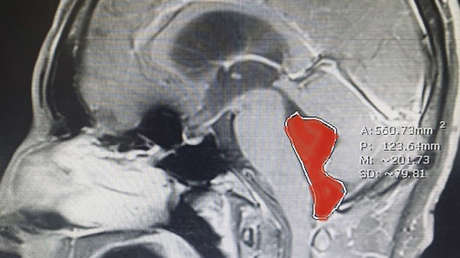

En mayo del año pasado se llevó a cabo una cirugía de emergencia para extirpar el parásito, que medía casi 4 centímetros, detalló este viernes The Washington Post. Según el diario, si la intervención quirúrgica se hubiera demorado, el incremento del líquido cefalorraquídeo hubiese aumentando la presión en el cráneo, poniendo en riesgo la vida del hombre.

"Es un caso notable, donde un paciente llegó y, si no hubiera sido tratado de urgencia, podría haber muerto por la presión tremenda en el cerebro", afirmó este jueves el doctor Jordan Amadio, neurocirujano del Centro Médico Dell Seton. Señaló que el caso no se hizo público hasta que el paciente se recuperó y regresó a su vida normal.